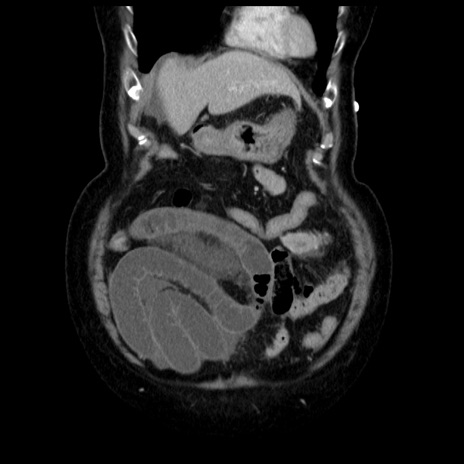

症例13(冠状断像)

【症例】70歳代女性

【主訴】腹痛、嘔吐

【現病歴】15時間程前(昨晩)より腹痛あり。今朝になっても症状の改善なく、嘔吐あり。腹痛も増悪あり、救急外来受診。

【既往歴】子宮癌全摘術後

【身体所見】意識清明、BP 121/72mmHg、P 74bpm、SpO2 100%(RA)、腹部:平坦・軟、腸雑音ほぼ聴取せず。下腹部・心窩部・臍左上に圧痛あり。反跳痛なし。

【データ】WBC 10600、CRP 0.15